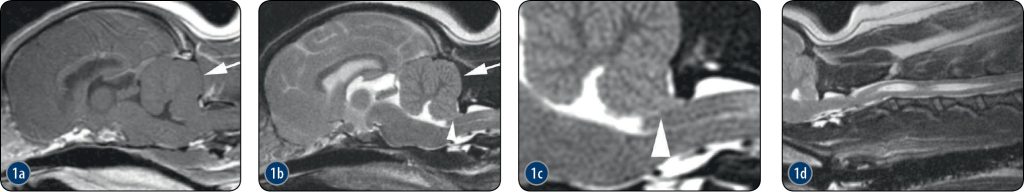

Malformacja typu Chiari jest spowodowana zmniejszoną objętością doogonowego dołu czaszki, co prowadzi do niedopasowania objętości móżdżku do objętości doogonowego dołu czaszki. Choroba ta występuje głównie u psów rasy cavalier king charles spaniel, ale może dotyczyć również przedstawicieli innych ras małych i miniaturowych. Zmniejszona objętość dołu doogonowego czaszki skutkuje stłoczeniem i przemieszczeniem móżdżku, który w niektórych przypadkach może się wpuklać lub przepuklić przez otwór wielki. Stłoczenie móżdżku powoduje również ucisk pozamózgowy komory czwartej i kanału centralnego, co prowadzi do wodogłowia obturacyjnego i jamistości rdzenia kręgowego (syringohydromyelii). Objawy kliniczne obejmują ból, ból pozycyjny, przeczulicę oraz deficyty neurologiczne, jednak ich nasilenie słabo koreluje z wynikami badań obrazowych.

Na obrazach TK doogonowy dół czaszki wydaje się mniejszy niż normalnie, co można najlepiej ocenić na obrazach w rekonstrukcji strzałkowej. Można również zaobserwować wodogłowie obturacyjne i jamistość rdzenia kręgowego. Podobne cechy są widoczne na obrazach MR, a sekwencja strzałkowa T2-zależna często jest najbardziej przydatna do wykrywania poszerzenia komór i kanału centralnego oraz do rozpoznawania przemieszczenia móżdżku i przepukliny przez otwór wielki (ryc. 2.3.1, 2.3.2).